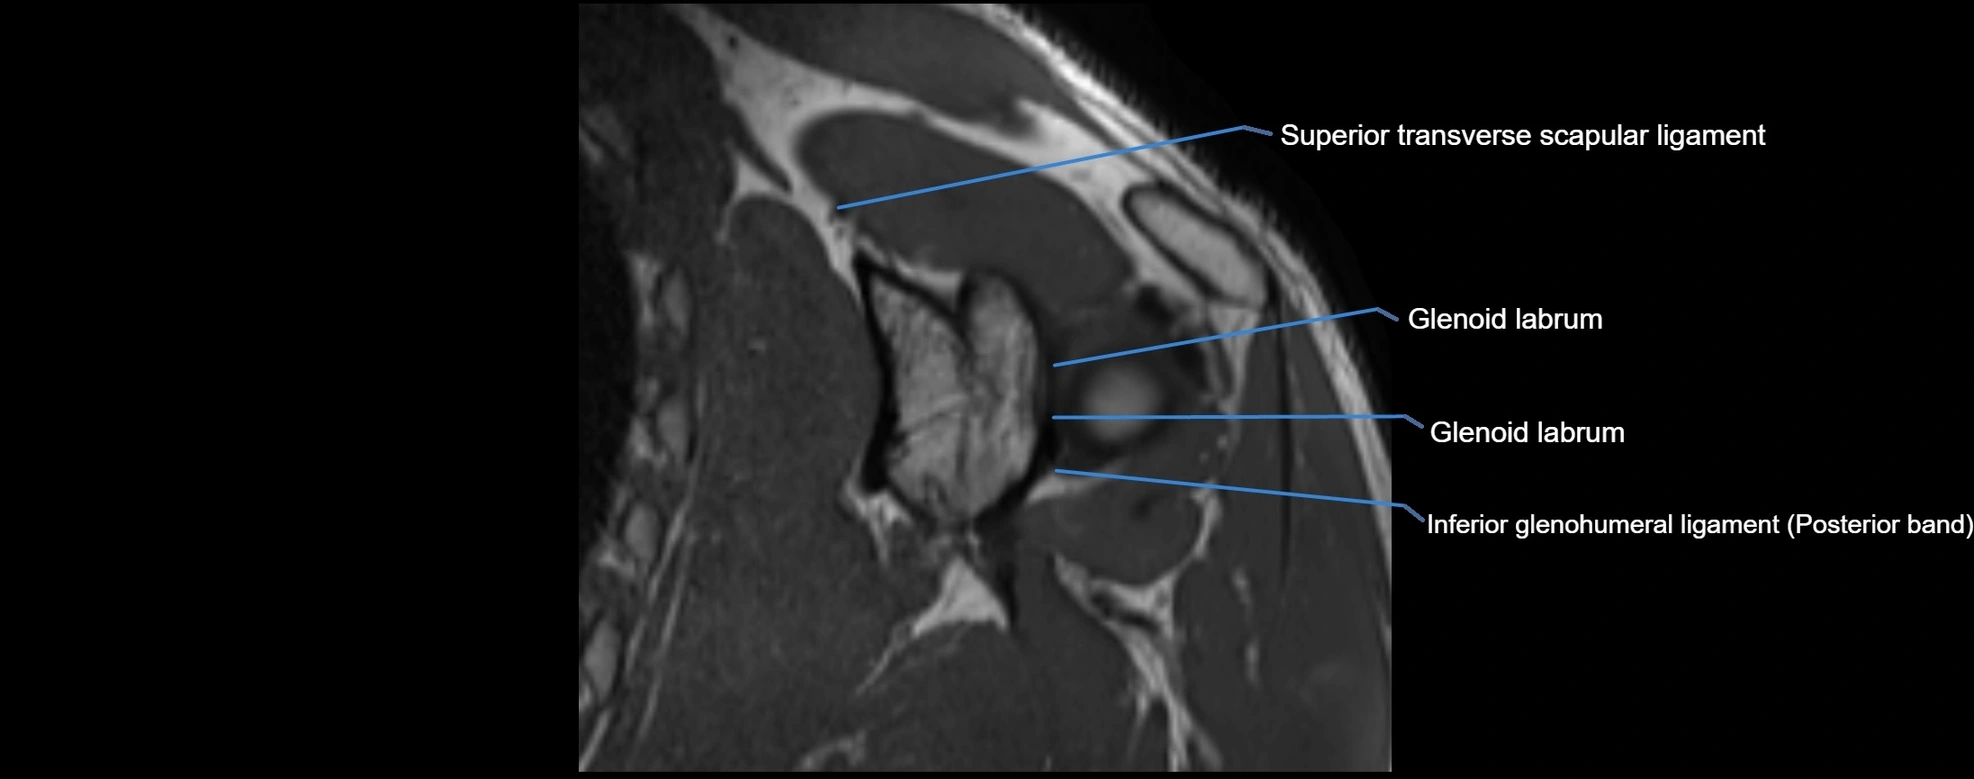

MRI images

image

MRI Appearance

• T1-weighted images:

• Normal ligament: Low signal (dark linear band) spanning acromion to clavicle.

• Surrounding fat planes: Bright, delineating the ligament clearly.

• Marrow of clavicle and acromion: Bright due to fatty content.

• Tears: Discontinuity or irregular thickening with intermediate-to-bright signal.

• Chronic injury: Thinning, fraying, or irregular low-signal fibers with adjacent scarring.

• T2-weighted images:

• Normal ligament: Low signal, homogeneous.

• Partial tear or sprain: Focal hyperintensity or thickening.

• Complete tear: Discontinuity with fluid-bright gap between clavicle and acromion.

• Associated edema: Bright signal in distal clavicle or acromion marrow.

• STIR:

• Normal ligament: Dark linear band.

• Injury or inflammation: Bright hyperintense signal in and around ligament fibers.

• Highlights periligamentous soft-tissue edema, especially in acute trauma.

• Proton Density Fat-Saturated (PD FS):

• Normal ligament: Low signal, uniform thickness.

• Partial tear or sprain: Bright signal or contour irregularity.

• Complete tear: Clear discontinuity with bright signal gap and joint effusion.

• Excellent for assessing joint capsule, coracoclavicular ligaments, and periarticular edema.